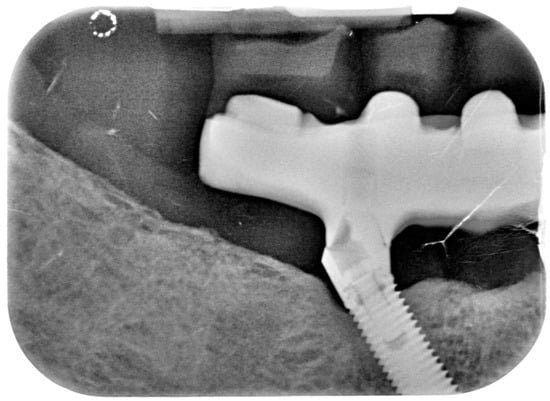

Figure 11.

X-ray of 4.5 dental implant in patient before treatment.

Figure 14.

X-ray of 4.5 dental implant in patient in 6 months after treatment.